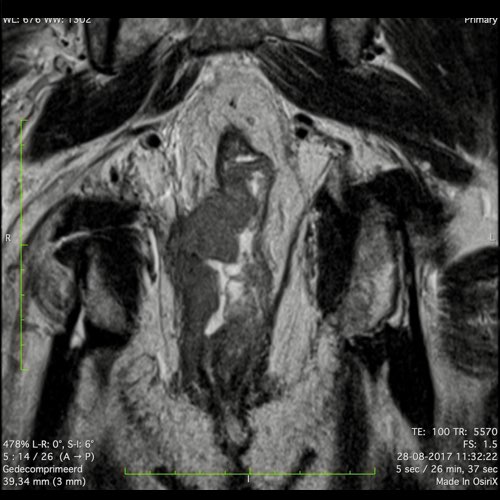

Hình ảnh

Các hình ảnh được cung cấp cho thấy ung thư biểu mô tế bào nhẫn với tình trạng dày lan tỏa thành trực tràng, hình ảnh bia bắn điển hình, và sự xâm lấn mỡ mạc treo trực tràng.